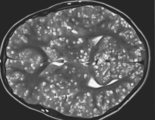

Muere con 18 años con el cerebro lleno de larvas tras comer carne cruda

El chico acudió al servicio de urgencias después de sufrir convulsiones y dolores en todo el cuerpo. La infección se produjo por comer carne cruda.